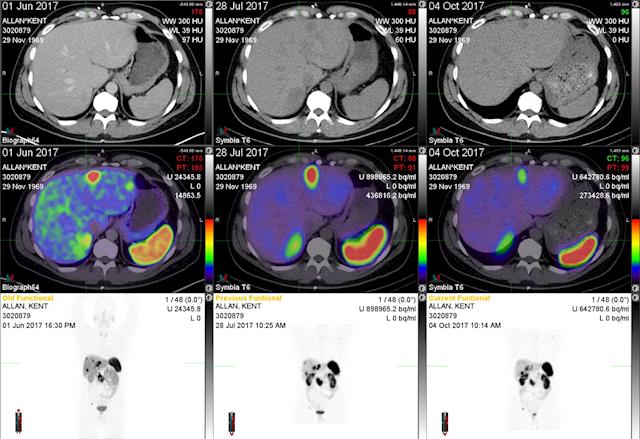

I'm trying to upload a scan so you can see the changes after each treatment.

in 2015 his cancer cells transferred to the liver, pancreas and other parts. He had been told from the doctor that he may only have about two years to live. The new scan in April this year found that the tumors had quadrupled in size only 1 year after the last scan, and he needs to travel to Melbourne to have further treatment to extend his live. This treatment is called Peptide Receptor Radionuclide Therapy (PRRT), the cost is about $50,000 and is known to prolong life by 5 years.

2015年他的癌细胞转移到了肝,胰腺等部位,医生告知他的生命也许只有两年左右。今年四月的扫描发现他的那些肿瘤数量比一年前翻了两番。他需要到澳大利亚墨尔本去做一种特殊的治疗来延长他的生命。这种治疗称为肽受体放射性核素治疗(PRRT),费用大约是5万元,但已知可将生命延长大约5年。